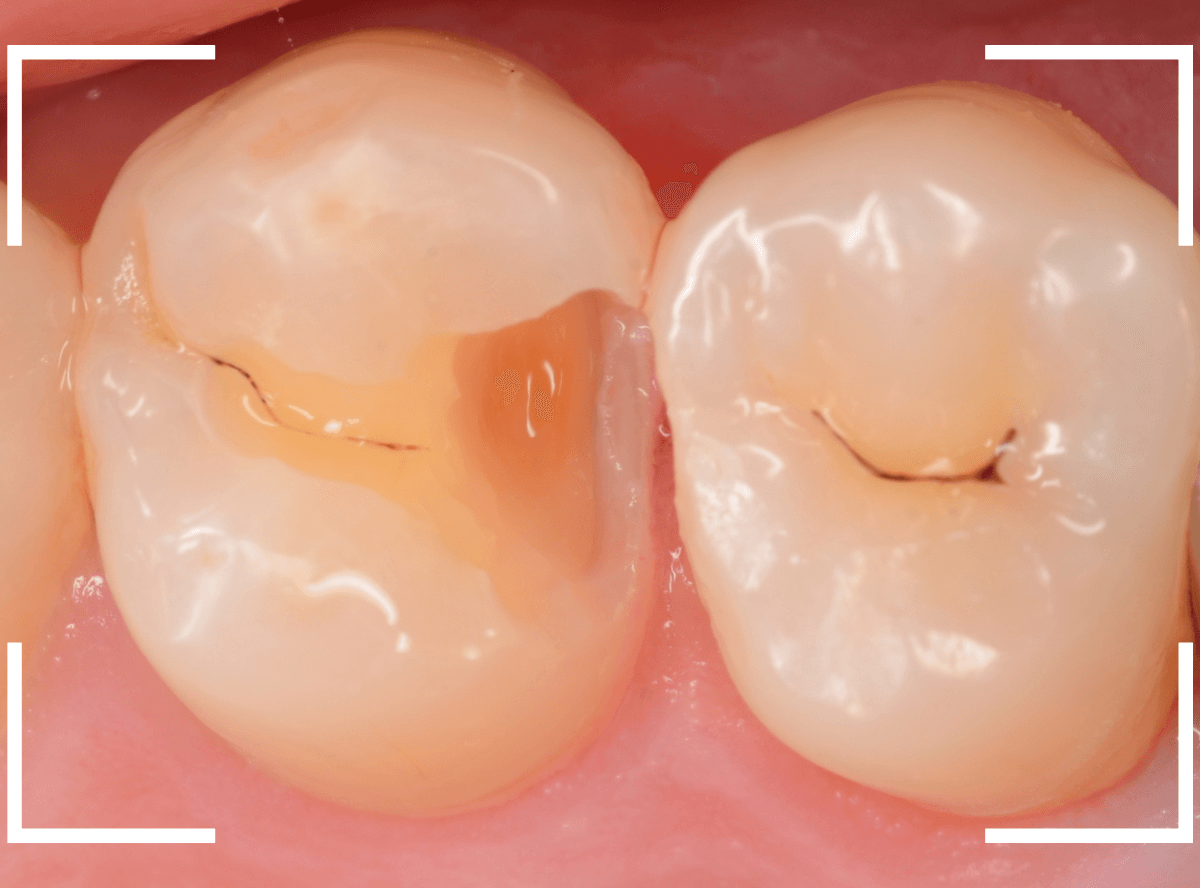

Case.14 CR(コンポジット・レジン)の下の深い虫歯

奥歯で咬んだ時に、痛みを感じるという訴えで来院された患者さんです。

パッと見は特に問題なさそうな状態ですが、大きなレジン治療がしてあり、レジンの奥もボヤっと黒っぽく見えてアヤシイ感じです。

麻酔をして、治療を開始します。

レジンを外すと、中から出血してきました。

これは、歯のスキマに歯肉が入り込んでしまったために起こってしまったものです。

おそらく、随分前から虫歯が進行していたと思われます。